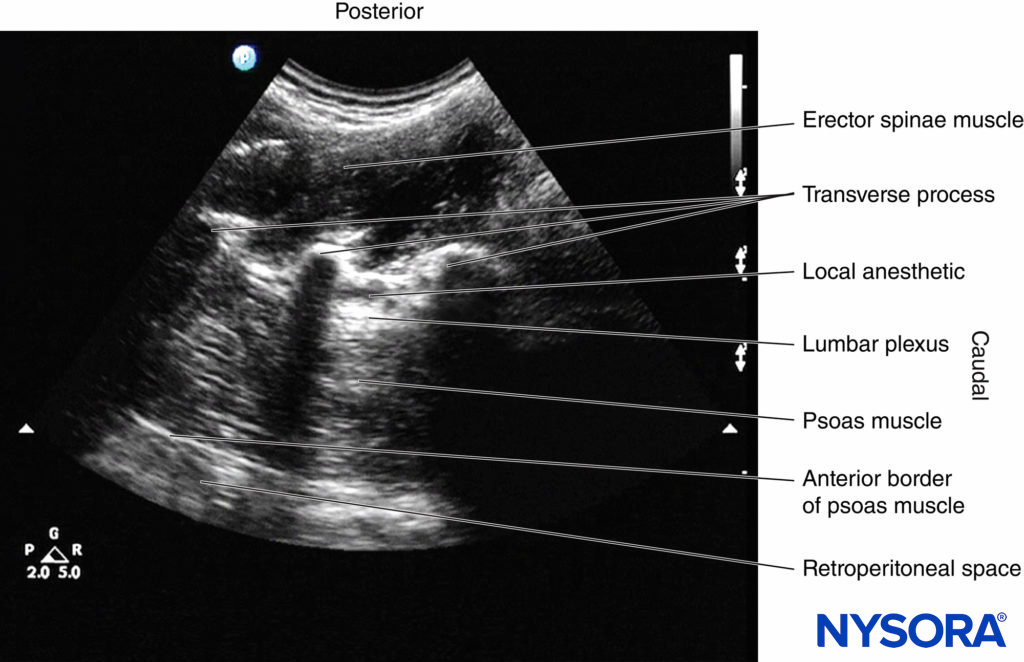

3. The Shamrock Method

Sauter and colleagues recently described an alternative approach for USG LPB, which they refer to as the “shamrock method (Figure 24b).” As described above, a transverse scan is performed at the flank and immediately above the iliac crest, with the patient in the lateral position and with the side to be blocked uppermost (see Figures 15a,b and 24b). Once the sonographic pattern of the “shamrock” is obtained at the level of the L4 transverse process (see Figure 16), the US transducer is tilted slightly caudally until the acoustic shadow of the transverse process is no longer visualized (see Figure 17).

This view represents the transverse view of the anatomy relevant for LPB through the L4–5 intertransverse space. A line is then drawn on the patient’s back extending from the center of the medial end of the IS transducer to the midline (back). A nerve block needle is inserted 4 cm from the midline along this line (Figure 28) and gradually advanced anteriorly under real-time US guidance (in-plane needle insertion; Figure 29a) until the needle tip is close to the L3 nerve root. Nerve stimulation should be used in conjunction with US to confirm correct needle placement, after which 20–30 mL of ropivacaine or levobupivacaine 0.5% is injected slowly while visualizing the perineural spread of the drug in the posterior aspect of the psoas muscle (Figure 29b).

The technical challenge with this approach is that although the block needle is inserted in plane, visualizing the needle initially can be very challenging, since the sites for the US scan and needle insertion are separated by a considerable distance (see Figure 28). Nevertheless, with experience, needle visualization can be easily accomplished.